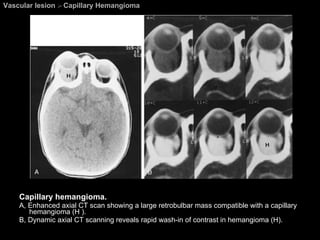

Capillary Hemangioma (Benign Hemangioendothelioma)   The most common orbital vascular tumor in  infants . Occur in the first year of life.  The tumor often increases in size for 6 to 10 months and then gradually involutes. Most commonly in the  superior nasal quadrant .

Capillary Hemangioma (Benign Hemangioendothelioma)   Location : entirely extraconal or substantial extraconal component.  CT findings: Lobulated, irregularly marginated, and heterogeneous. Intense homogeneous enhancement. MRI findings: hypointense or slightly hyperintense to brain on T1WI. hyperintense to brain on PDWI and T2WI. intense enhancement.

Vascular lesion  >  Capillary Hemangioma Capillary hemangioma.  A, Enhanced axial CT scan showing a large retrobulbar mass compatible with a capillary hemangioma (H ).  B, Dynamic axial CT scanning reveals rapid wash-in of contrast in hemangioma (H).